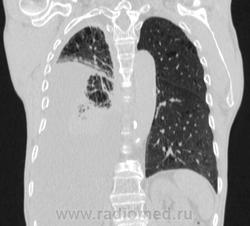

Пожилой мужчина, лечился по н/д правостороннней пневмонии в терап/отделении. Жалобы на одышку, кашель. По результатам Р-контроля после лечения направлен на КТ легких с диагнозом: плеврит справа, распад? В корне правого легкого вижу объёмное образование, с распадом. Смущают размеры плеврита,очень много жидкости, почти до 3 ребра. Анализы крови спокойные- L4,0-6,6, СОЭ 12-16мм. Неужто ТБС, отсев бы был при таком огромном поражении. В посеве мокроты-100% высев клебсиэллы пневмоние. Мокрота на общий анализ в работе-собирает с трудом, изза отсутствия мокроты. Плевральную пункцию еще не проводили. Н азначила бронхоскопию и плеврал пункцию. Как думаете, уважаемые коллеги, это онкопроцесс или тбс распад?

Коллеги, распада там нет, это вас медиастинальное окно подвело. В грудине тоже все в порядке. Да и компрессия позвонка "старая".

Небольшое количество увеличенных лимфоузлов, и те - не сказать, чтоб были очень крупными. От эмпиемы до онкологии... Умеренное количество жидкости в перикарде, толщиной слоя до 13-14 мм. При подобной картине не вижу смысла гадать по сжатому лёгкому, пишу так: массивный выпот справа, около 2500 мл, диафрагма оттеснена жидкостью каудально, печень (!!!) смещена каудально и вправо. Легкое справа значительно компрессировано жидкостью, оценка проходимости бронхов и состояния легочной паренхимы (кроме имеющейся эмфиземы) практически невозможна. Необходима пункция плевральной полости справа (цитология, ВК, посев на микрофлору и проч), КТ-контроль после эвакуации жидкости.